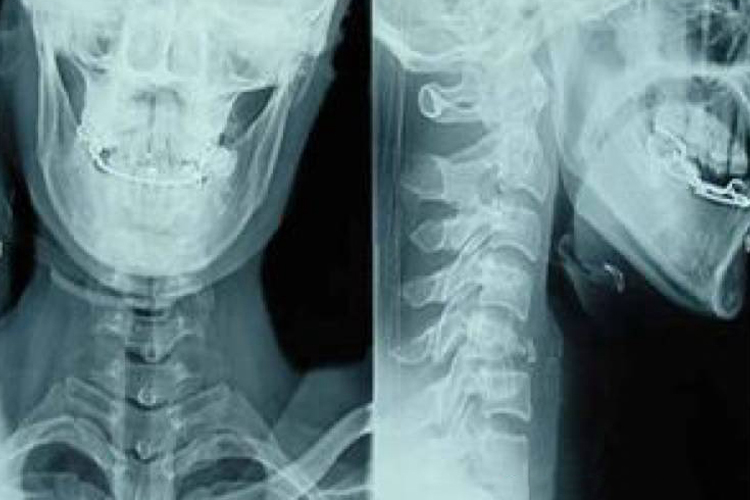

颈椎半脱位好发于第1、2颈椎之间,最常见的症状是头颈部疼痛,向上放射至枕部,颈部活动受限,转动颈部时疼痛加重。颈部肌肉紧张痉挛,棘突上多有压痛。临床检查有神经根刺激症状或受牵扯症状。X线可见生理性前凸消失,伤侧及两侧椎间隙不对称。